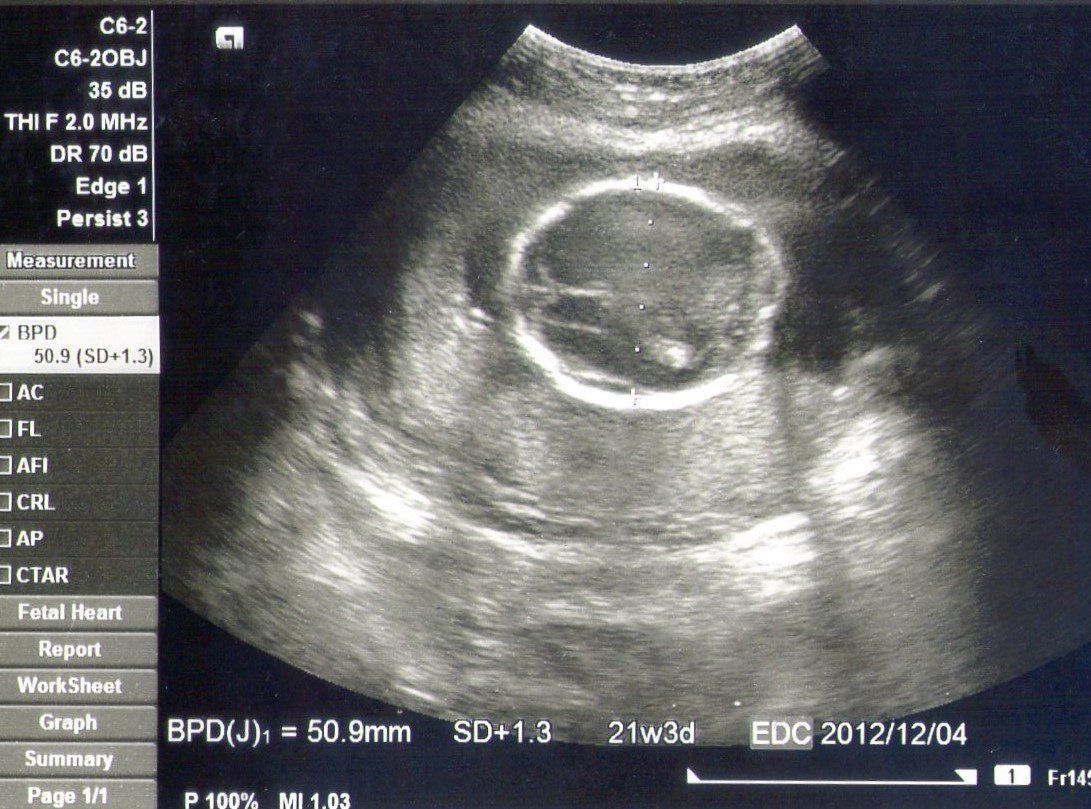

妊娠20週目のエコー写真 初めての助産師外来

BPD=50.9㎜

赤ちゃんの頭のエコー写真です。私が通っていた産院では助産師外来があり、食事の指導や体の変化や不調に対する相談をすることができました。自分では自覚がなかったのですが、おなかが張りやすいと言われました。立ち仕事が多かったせいかもしれません。